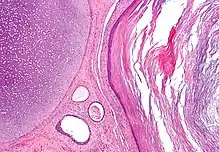

The ectoderm generates the outer layer of the embryo, and it forms from the embryo's epiblast.[13] The ectoderm develops into the surface ectoderm, neural crest, and the neural tube.[14]

The surface ectoderm develops into: epidermis, hair, nails, lens of the eye, sebaceous glands, cornea, tooth enamel, the epithelium of the mouth and nose.